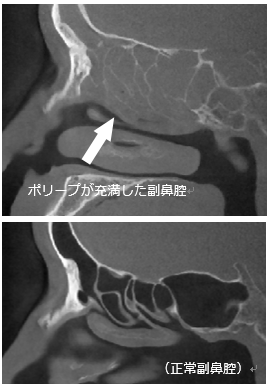

副鼻腔は吸ったり吐いたりする空気が中を循環して加湿されたり清浄されるための小部屋の集まりです。それぞれの「部屋」は空気や鼻汁(鼻みず)の自然の出入り口(自然孔)を持っていますが、この自然孔が細菌やウイルスによる感染、アレルギーの影響などにより粘膜が腫れてつまってしまい、換気が悪くなると副鼻腔内に膿やポリープが充満してくる「副鼻腔炎」と呼ばれる状態になります。

鼻茸(ポリープ)が充満している場合は鼻洗浄や点鼻薬だけでは症状が改善しないことが多いため、手術治療を勧めることがあります。

手術では、点鼻薬や鼻洗浄だけでは消失しないポリープなどを取り除き、副鼻腔の自然孔を拡大したり、不要な壁を切除したりしていきます。